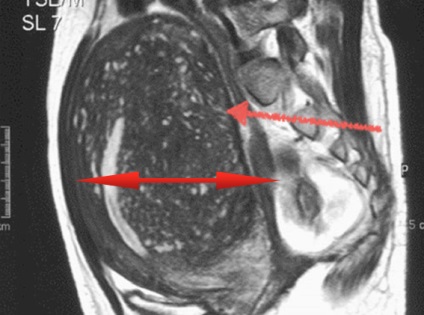

RMN-ul a bazinului. endometrioza. Uterul este extinsă și corespunde 7-8 săptămâni de sarcină (dar pacientul nu este gravidă, doar atât de mult o consecință a uterului în endometrioza). Multiple de comutare indicată de săgeată.

Prezentarea clinică depinde de localizarea formării patologice, dar comune simptome sunt durere, tulburari ale ciclului menstrual, infertilitate. În legătură cu diferite exemple de realizare ale aranjamentului vatra, RMN-ul este principala metoda de diagnostic non-invaziva. In imagini T1-ponderate endometrioza apare vatra ca intensitate ridicată cu contururi precise capsulei fibroase datorate, care se formează în jurul formarea de orice dimensiune. Pentru T2-tomografii simptom caracteristic al umbrire, focalizarea are o intensitate de colorare redusă.

Adenomioza, endometrioza este o variantă în care proliferarea endometrului se produce în grosimea miometrului uterin.

În forma adenomioza difuză are aceeași intensitate la țesuturile înconjurătoare, pot conține mici focare pătat de intensitate crescută care ajuta la diagnostic. Când formarea leziunii focale are o intensitate ridicată pentru ambele moduri, contururi uterine deformate.